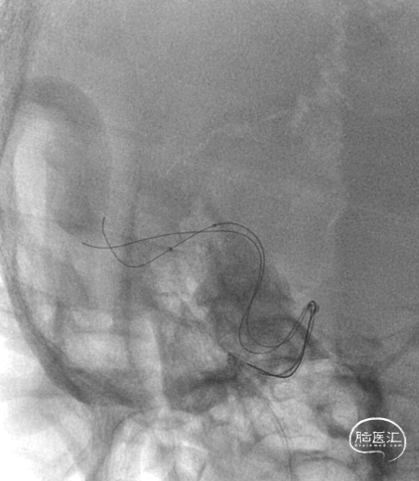

右侧大脑中动脉M1分叉处局部重度狭窄,约80%。

Connect 300cm V18导丝内支撑,2根200cm snychro-2微导丝分别超选至M2上下干。

1.5*10mm 球囊先扩下干,并造影,可见局部狭窄明显改善。